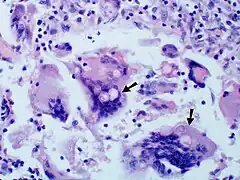

Once suspected, the diagnosis of blastomycosis can usually be confirmed by demonstration of the characteristic broad based budding organisms in sputum or tissues by KOH prep, cytology, or histology.[17]

Tissue biopsy of skin or other organs may be required in order to diagnose extra-pulmonary disease. Blastomycosis is histologically associated with granulomatous nodules. Commercially available urine antigen testing appears to be quite sensitive in suggesting the diagnosis in cases where the organism is not readily detected. While culture of the organism remains the definitive diagnostic standard, its slow growing nature can lead to delays in treatment of up to several weeks. However, sometimes blood and sputum cultures may not detect blastomycosis.[18][16][15]

Large yeast-like fungi seen within giant cells at arrows. -

Large yeast-like fungi seen within giant cells at arrows.Budding yeasts in cytoplasm of giant cells at arrows. Broad-based budding and double contoured cell wall seen in the giant cell in the center is characteristic of Blastomyces dermatitidis.